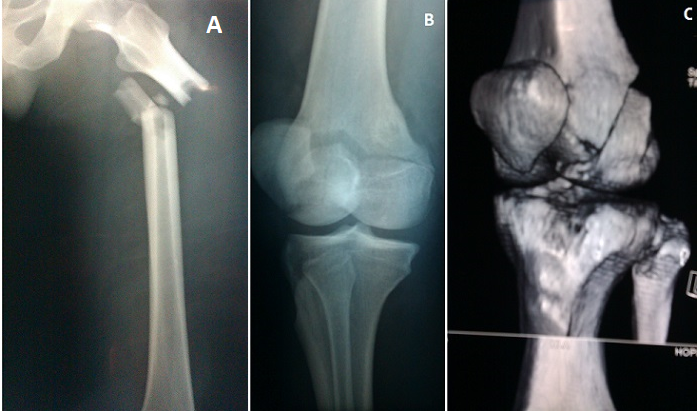

L'association fracture de la diaphyse fémorale et fracture de Hoffa de l'extrémité inférieure du même fémur est très rare, peu de cas sont décrit dans la littérature. Elles surviennent après un traumatisme à haute énergie surtout lors des accidents de la voie publique. Elles touchent par conséquent une population jeune. Notre patient est âgé de 27 ans, il a été victime d'un accident grave en conduisant sa moto. Le diagnostic est évoqué devant l'association d'une déformation de la cuisse et une hémarthrose du genou. L'examen vasculo nerveux doit être systématique par la palpation des pouls distaux et exploration du SPE et SPI. La confirmation diagnostique est faite après un bilan radiologique comprenant une radiographie standard de tout le fémur et des radiographies de face, profil et ¾ du genou éventuellement complétées par une TDM avec reconstruction 3D permettant de mieux visualisé la fracture de Hoffa. Le traitement est chirurgical consistant en enclouage centromédullaire à foyer fermé de la fracture du fémur, associé à un vissage percutané ou à foyer ouvert de la fracture de Hoffa en fonction des possibilités réductionnelles. Le pronostic est dominé par le risque important de raideur du genou.